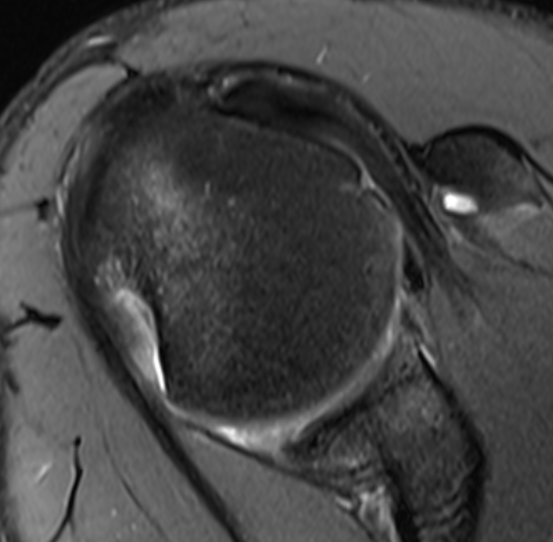

MRI

Anterior labral tears

Bony bankart / anterior glenoid deficiency